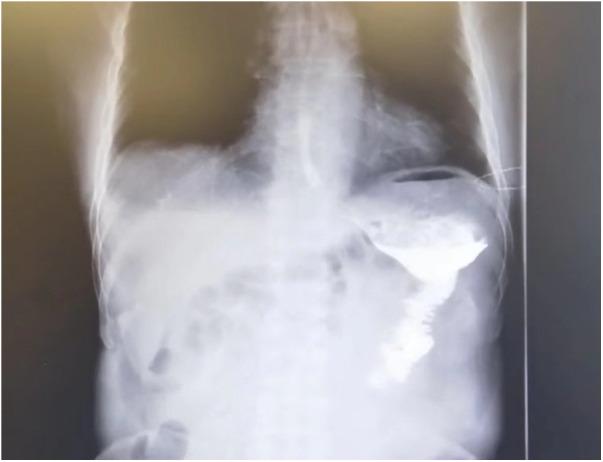

Although there were a variety of strategies for the alimentary tract reconstruction of patients with gastric cancer who underwent laparoscopic radical distal gastrectomy, it remains controversial regarding which procedure is optimal. We developed a simple technique for Roux-en-Y reconstruction during laparoscopic surgery and evaluated its technical feasibility and safety.

Seventy-one cases of modified Roux-en-Y reconstructions after laparoscopic radical distal gastrectomy were consecutively performed in our hospital, from November 2020 to March 2022. A retrospective review of medical data was conducted. Intraoperative and postoperative outcomes, including operation time and incidence of postoperative complications, were collected and analyzed.

All procedures of laparoscopic distal gastrectomy with D2 lymph node dissection were successfully completed without any intraoperative complication. The mean number of retrieved lymph node was 38.8 ± 10.6. Mean operative time was 223.5 ± 42.4 min, whereas intraoperative blood loss was 102.2 ± 96.3 ml. No postoperative mortality was recorded. Six patients (8.5%) experienced postoperative complications and were managed conservatively. In addition, only two patients (2.8%) required rehospitalization during a median short-term follow-up period of 6 months.

The modified method is a simple and safe approach for laparoscopic radical distal gastrectomy.